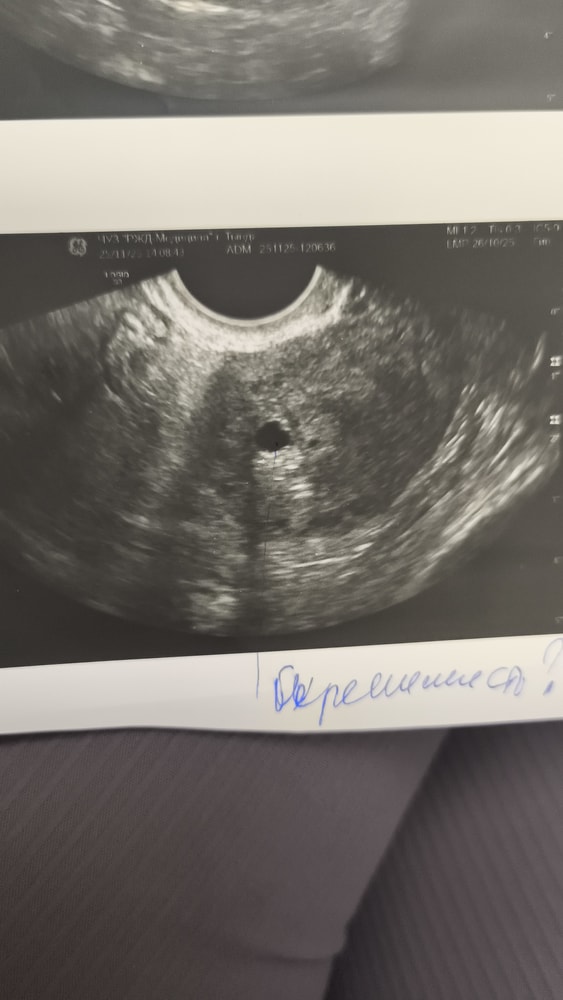

Маруся, маленький уже в матке Изображение

Диана , только что с узи, толь пя, угроза выкидыша

Женечка , только с узи пя в матке, угроза выкидыша Изображение

Наталия Алиева, спасибо большое. Все препараты принимаю. Экстренно на узи увидела пя в матке 4,5 мм, думала не увидят. По месячным 4 н 2 д. Уже радует, что маточная.